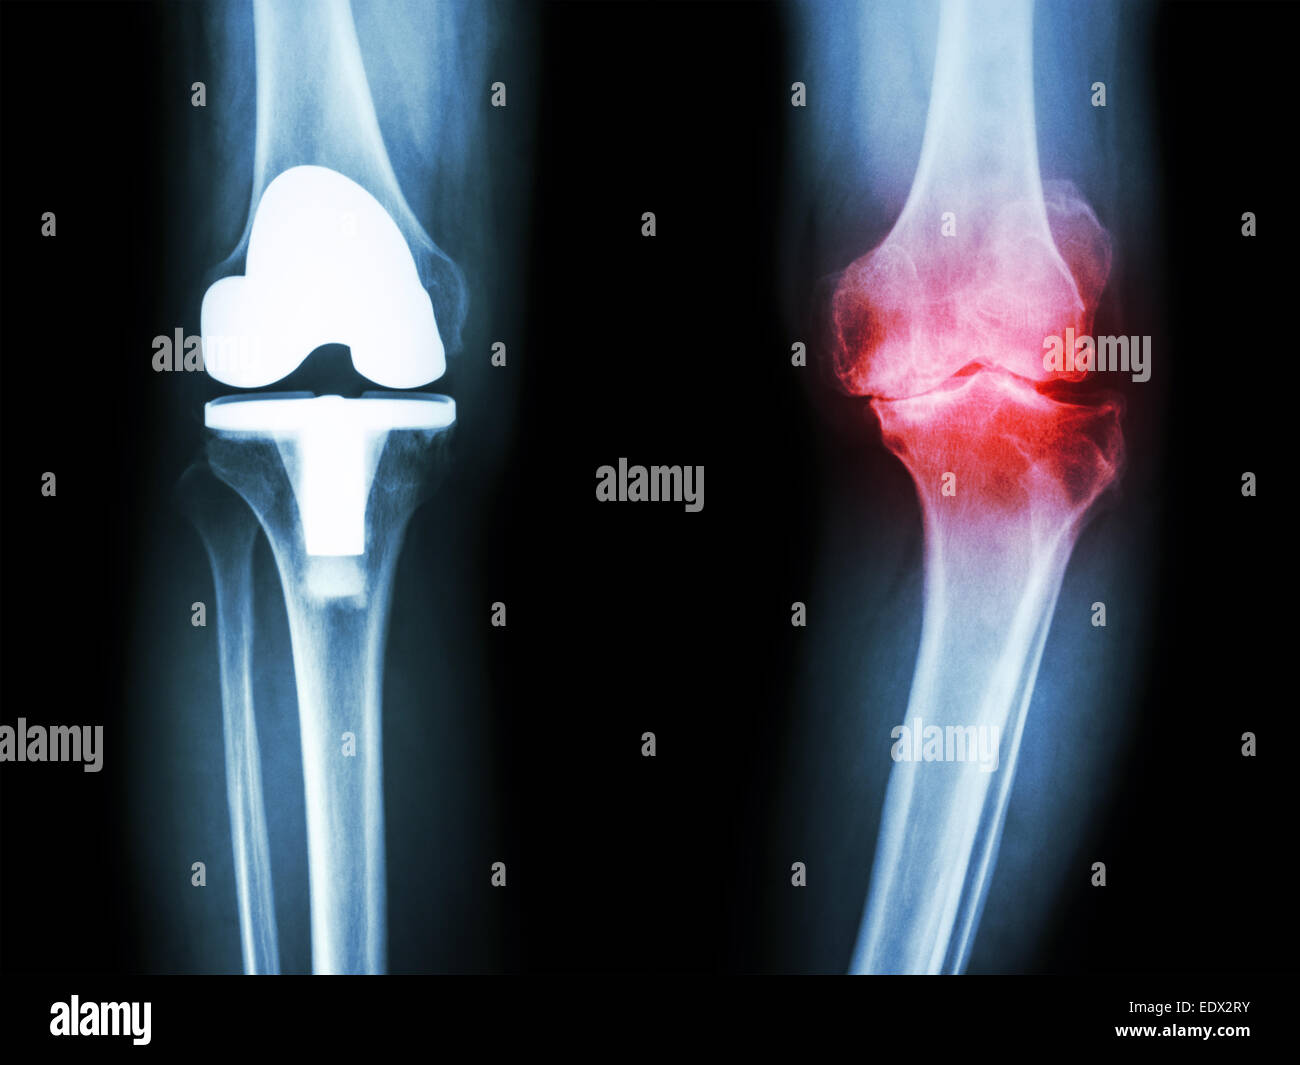

Synthetic Joint . It’s a structure that replaces a knee severely damaged by arthritis. They help the knee bones and cartilage to. what you might casually refer to as a “fake knee” is known as an artificial knee or a knee replacement. in wear tests, the researchers took artificial cartilage and natural cartilage and spun them against each other a. synvisc injections help to improve the lubrication and cushioning of the knee joint caused by the cartilage damage. scientists from duke university have developed a new synthetic cartilage they say can feasibly work even in the human knee.

From www.alamy.com

Knee joint prosthesis (Artificial joint) of osteoarthritis patient Synthetic Joint what you might casually refer to as a “fake knee” is known as an artificial knee or a knee replacement. It’s a structure that replaces a knee severely damaged by arthritis. scientists from duke university have developed a new synthetic cartilage they say can feasibly work even in the human knee. synvisc injections help to improve the. Synthetic Joint.